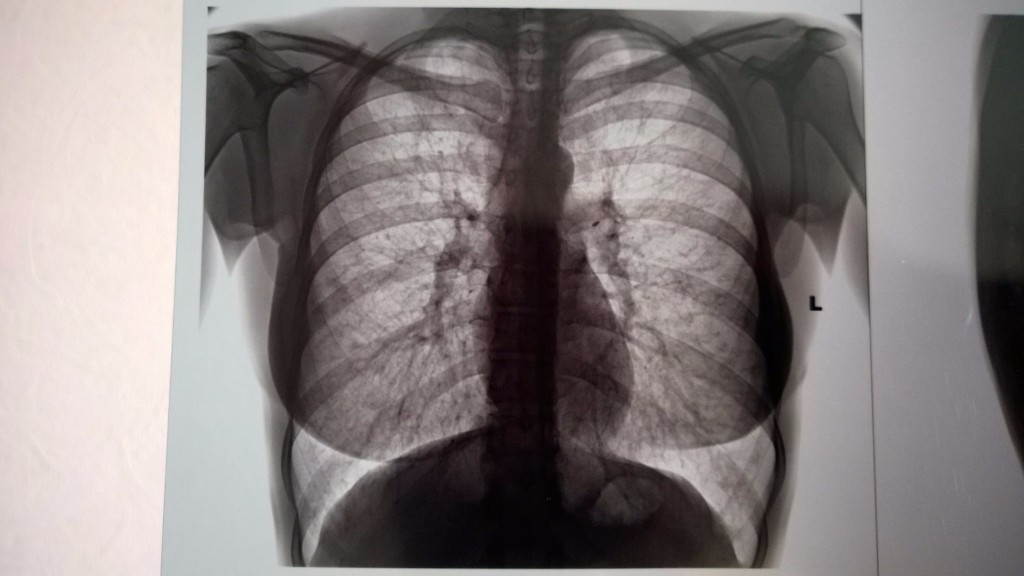

Нормальная рентгенограмма легких: что нужно знать

Раздел: Мудрость в объективе